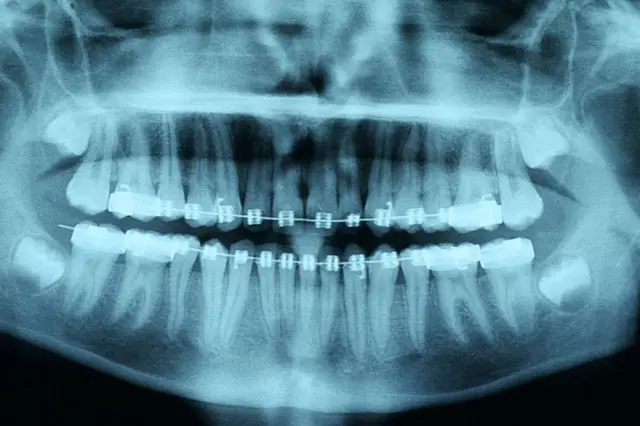

Algunos de los factores que tienen en cuenta los dentistas para recomendar su uso es la salud de los tejidos duros y blandos de la boca, los dientes y las encías, así como si las raíces de los dientes pueden sostener un movimiento. Por eso es que las radiografías son fundamentales en este proceso.

Las raíces de los dientes del paciente eran demasiado cortas para soportar la presión de los alineadores, lo que se habría detectado en una radiografía.

Según las asociaciones dentales británicas, los escáneres 3D y los moldes de dientes que se hace uno mismo utilizados en ortodoncia a distancia no son suficientes para recomendar el uso de alineadores.

Como ejemplo, la BBC le mostró al doctor Crouch tres imágenes interactivas en 3D de los dientes que muestran cómo podrían moverse durante el tratamiento que SDC presenta a clientes potenciales.

El doctor dijo que dos de ellos mostraban signos visibles de enfermedad de las encías, lo que significaba que los alineadores podrían "aflojar los dientes lo suficiente como para provocar su pérdida".

El tercer plano, en caso de ser aceptado, podría dejar a esa persona con una mordida inestable.